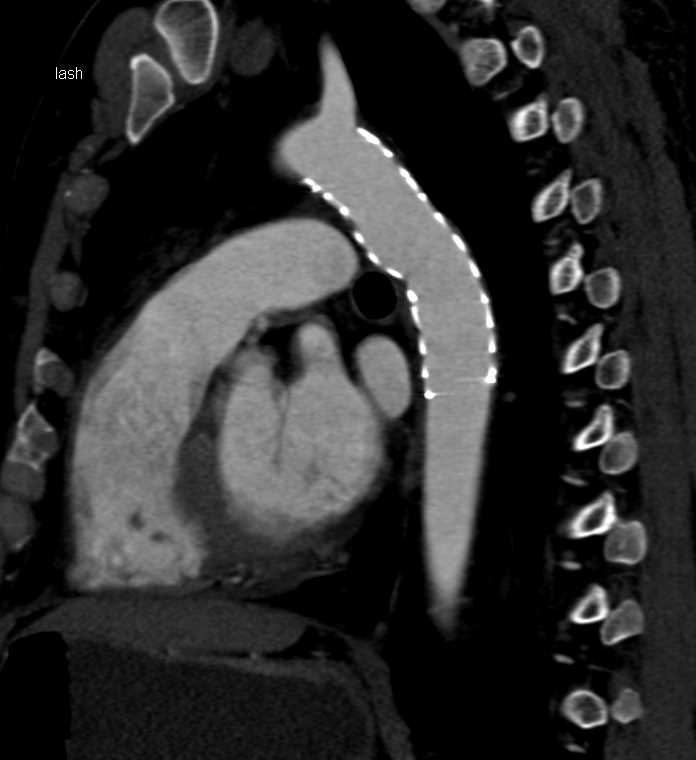

Acute descending thoracic aortic dissection is a dramatic and potentially catastrophic condition. The emergence of thoracic endovascular aortic ... Read Document

Thoracic Aortic Dissection: Long-Term Results of Endovascular and Open Repair Sreekumar Subramanian, MD, and Eric E. Roselli, MD Treatment paradigms for aortic dissection are based upon the types of complications with ... View Document

While thoracic aortic dissec-tions are uncommon, Management of Acute Aortic Dissection and the International Registry of Acute Dissection Figure. an initial surgical repair or successful nonoperative hospi- ... Fetch Document

Aortic Dissection: Advances In Imaging And Endoluminal Repair

REVIEW ARTICLES Aortic Dissection: Advances in Imaging and Endoluminal Repair Bernard D. Prendergast, 1Nicholas A. Boon, Timothy Buckenham2 1Department of Cardiology, The Royal Infirmary of Edinburgh, Lauriston Place, Edinburgh EH3 9HW, UK ... Retrieve Here